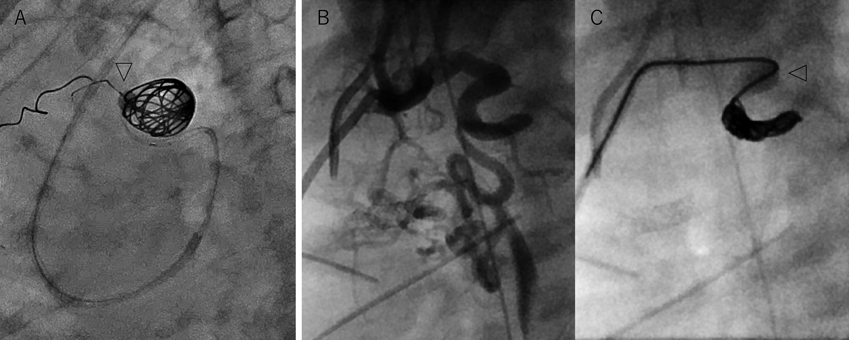

Fig. 6 Stop flow法での塞栓例

A)冠動脈肺動脈瘻の成人症例.短絡血流が速く,塞栓する瘤の遠位側をLOGOS™バルーン(矢頭)で閉塞した状態で瘤をコイルで充填して塞栓した.B, C)太く血流の速いMAPCA.肺動脈への脱落迷入リスクがありPinnacle Blue™ 20バルーンで近位を閉塞し(矢頭),先端からコイルを留置した.